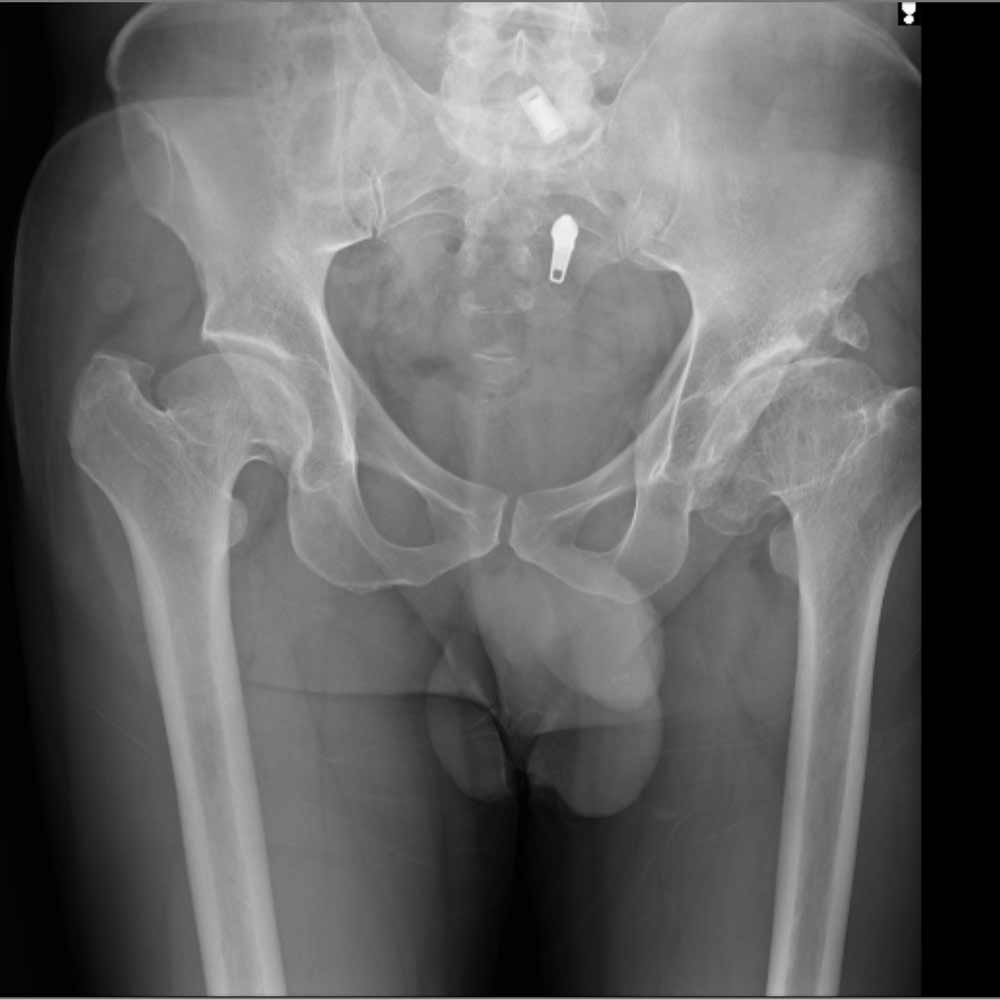

در نهایت، روش های تصویر برداری مثل رادیوگرافی به تشخیص بیماری کمک میکند. مهمترین روش تصویربرداری برای تشخیص ساییدگی لگن رادیوگرافی ساده است. تشخیص این بیماری نیاز به سی تی اسکن یا ام ار آی ندارد.

در تصویر رادیوگرافی از مفصل، چون غضروف نازک شده است فاصله مفصلی یا فاصله بین دو استخوانی که مفصل را تشکیل داده اند و در حد چند میلیمتر است کاهش پیدا میکند و در کناره های استخوان های تشکیل دهنده مفصل استخوان اضافی دیده میشود.

همچنین ممکن است کیست های استخوانی در بالای استابولوم یا در سر استخوان ران دیده شود.

در زیر تصاویری از عکس ساییدگی لگن در چند بیمار را میبینید. با کلیک بر روی هر کدام تصویر بزرگتری از آن را خواهید دید.